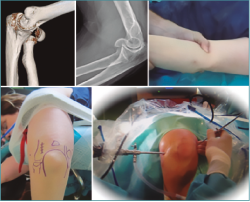

Figura 9. Radiografías y tomografía axial computarizada de fractura supraintercondílea.

Figura 10. Colocación del paciente, visión articular de la fractura y reducción artroscópica.

Figura 11. Fijación interna con 3 tornillos canulados, control por escopia y artroscópica.

Figura 12. Resultado final.

Las fracturas que se presentan con una mínima inflamación son susceptibles de fijación artroscópica asistida. El hematoma y los restos articulares se eliminarán y usaremos una o varias AK para reducir la fractura percutáneamente (Figuras 9 a 12) colocando a continuación tornillos canulados en la columnas medial o lateral del húmero. Se debe usar el fluoroscopio para evitar introducirlo dentro de la fosa olecraniana(11).